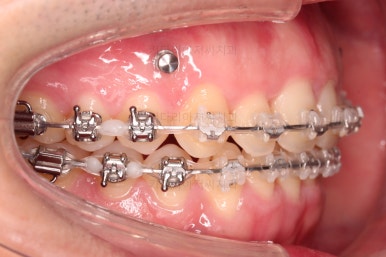

초진 시 입안의 모습입니다.

교합이 많이 안좋습니다.

위아랫니가 서로 엇갈려 가며 지그재그로 껴 들어가야 어금니 맞물림이 생기는데요.

이번 환자분은 아랫니, 아래턱이 전반적으로 앞으로 나와 있어서 교합이 전혀 안되고 있는 상태였습니다.